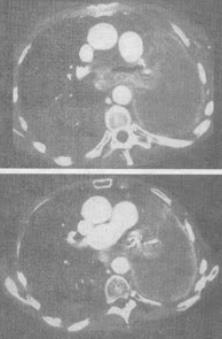

患者男,68岁,咳嗽,咯血2个月余,吸烟史40余年,结合影像学检查,最可能的诊断是()。

A、肺囊肿

B、肺癌

C、肺结核

D、肺脓肿

E、纵隔畸胎瘤

B